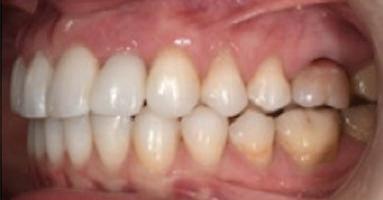

Dental Tribune Bulgarian Edition / октомври 2022 г.16 клиничен случай с алайнери Г орният латерален ре зец е вторият найчесто вродено липсващ зъб.1,2 Поради разполо жението му във видимата зона на усмивката лечение то на подобни случаи нала га мултидисциплинарен под ход, целящ отличен функцио нален и естетичен резултат. Налице са няколко лечебни мо далности, свързани с различ но разпределение на място то: първият вариант е орто донтско отваряне на място и възстановяване на липсва щия зъб с конструкция, под държана от съседните зъби3 или от имплант4, докато при втория подход разстоянията се затварят и премоларът заема мястото на канина.5 Изборът на лечебен подход трябва да бъде направен съв местно от зъболекар и паци ент въз основа на очакванията на последния и предвиди мостта на лечението. Множе ство фактори влияят върху това решение, като напри мер типа малоклузия, размера, формата и цвета на кучеш ките зъби6, оклузалните вза имоотношения (овърджет и овърбайт), лицевия профил, дължината на зъбната дъга и несъответствията в разме ра на зъбите.7 В настоящата публикация се разглежда случаят на жена в зряла възраст с вродена лип са на горен ляв латерален резец. Бяха приложени про зрачни алайнери за отваряне на място за единичен им плант и бяха постигна ти функционална оклузия и отлична естетика. ПРЕДСТАВЯНЕ НА СЛУЧАЯ Диагноза Пациентката бе на 32 годи ни, когато лечението започна, и първоначалното ѝ състоя ние бе следното (фиг. 1–3): липсващ горен ляв латерален резец; клас II, подклас I малоклузия; отклонение на горната сре динна линия вляво; Доклад на клиничен случай ЛЕЧЕНИЕ С АЛАЙНЕРИ НА ПАЦИЕНТ С АГЕНЕЗИЯ НА ЛАТЕРАЛЕН РЕЗЕЦ Д-р Iro Eleftheriadi и д-р Christodoulos Laspos, Гърция и Кипър Фиг. 1a–h Предоперативни лицеви и интраорални снимки. Фиг. 2a–e Дигитални модели преди началото на лечението. Фиг. 3 Панорамна снимка преди лечението. Фиг. 1a Фиг. 1d Фиг. 1f Фиг. 2a Фиг. 2d Фиг. 2b Фиг. 2e Фиг. 3 Фиг. 2c Фиг. 1b Фиг. 1e Фиг. 1g Фиг. 1h Фиг. 1c

Dental Tribune Bulgarian Edition / октомври 2022 г. 17клиничен случай с алайнери леко струпване в долната че люст; несъответствие по Болтън (мандибуларен излишък от 3.06 мм във фронталната зона и общо 1.47 мм); издължено лице с лицева аси метрия; конвексен профил с ретруди рана долна челюст и проми нентен нос. На мястото на зъб #46 бе на лице имплант, а зъби #16 и 26 са ендодонтски лекувани. Тези зъби бяха асимптоматич ни, затова бе взето решение да се прави релечение само при нужда. Мъдреците липсваха. Анализът на телерентгеногра фията (фиг. 4) показа ретрог натна мандибула (SNB: 74.2°) и нормална инклинация на резците както в

Цели на лечението и лечебен план Целите на лечението бяха следните: нивелиране и подреждане на зъбите и в двете зъбни дъги; отваряне на пространство за липсващия латерален резец; коригиране на отношенията при канините и моларите до клас I; и корекция на отклонението на срединната линия. Лечебният план включваше: корекция на отношенията при кучешките зъби и мола рите до клас I с дистализира не на максилата; отваряне на пространство в областта на #22 за поставя не на единичен имплант; корекция на срединната ли ния; и създаване на място за раз ширяване на зъб #12 и апрок симална редукция в долната челюст с цел подобряване на несъответствието по Болтън и осигуряване на подобра оклузия. Изпълнение на лечебния план Този случай бе изпълнен със системата за алайнери Invisalign (Align Technology). Одобреният първоначален лечебен план предвиждаше 49 алайне ра с дистализиране на задни те горни зъби до клас I (прибли зително с около 3.5 мм; фиг. 5). За бъдещия имплант в областта на липсващия латерал бе планирано пространство от 6.5 мм, докато във фронталния сегмент на долната челюст бе предвидена апроксимална редук ция. В дясната страна бутон за ластици клас II бе поставен на зъб #47 вместо на зъб #46, за да не се увреди короната на импланта. Понеже пациентката жи вееше в чужбина,

следните казуси: недобра оклу зия в дисталните зони по вре ме на дистализирането на гор ната челюст и накланяне на зъб #21 (фиг. 7). Последното се дължи на липсата на компози тен атачмънт на този зъб, каквото не бе зададено в пър Фиг. 4 Телерентгенография и цефалометричен анализ преди началото на лечението. Фиг. 5a–e Одобреният първоначален лечебен план. Фиг. 6a–h Снимки по време на лечението, показващи нуждата от внасяне на някои корекции. Фиг. 4 Фиг. 5a Фиг. 5d Фиг. 6a Фиг. 6d Фиг. 6f Фиг. 6b Фиг. 6e Фиг. 6g Фиг. 6h Фиг. 6c Фиг. 5e Фиг. 5b Фиг. 5c

планта бе поставена временна коронка (фиг. 10 и 11), докато бъде изготвена окончателна та. Бе постигнат отличен кра ен резултат. Меките тъка ни около импланта напълно заздравяха, което доприне се за перфектната хармония между бяла и розова естетика (фиг. 12–15).

Dental Tribune Bulgarian Edition / октомври 2022 г.18 воначалния план. Тези пробле ми бяха адресирани чрез допъл нителна поръчка на алайнери с торк контрол и зададено екст рудиране на задните зъби с цел установяване на добри оклузал ни контакти в дисталните об ласти, като бяха предвидени и оптимизирани атачмънти с контрол над корените за корекция на ангулацията на макси ларните резци (фиг. 8). Резултати от лечението Панорамната рентгено графия след ортодонтското лечение показа благоприятна паралелна позиция на съседни те зъби, подходяща за поставя не на имплант в областта на #22, както и конвергенция на ко рените на зъби #44 и 45 (фиг. 9), но преценихме, че няма да от деляме допълнително лечебно време за коригирането ѝ поради факта, че пациентката бе мно го доволна от постигнатия до момента резултат. След при ключване на лечението бяха постигнати отлични взаимо отношения клас I при мола рите и канините, а срединни

(LFH: 56.5 mm) и размерите на меките тъка ни останаха непроменени. На клонът на горните резци бе за пазен (Ui–FH: 115.8°), а долните резци бяха леко наклонени ве стибуларно (Li–APog: 30°; фиг. 16). ДИСКУСИЯ Липсата на зародиш на по стоянен горен латерален резец е налице при 3.5–6.5% от евро пеидната раса, като при жени е по-честа, отколкото при мъ жете в съотношение 3:2.8–10 Възможни са няколко лечебни подхода, включително замя ната му с преоформен канин, отваряне на място чрез орто донтско лечение и протетич но възстановяване, както и ав тотрансплантация. Устано вено е, че изборът за затваря не на място или за отваряне то му все още подлежи на дис кусия сред ортодонти и проте зисти.11,12 Според литературните дан ни затварянето на простран ството и замяната на липсва щия латерал с канин се предпо чита в случаи на едностранна липса на зародиш, балансиран профил, кучешки зъби и премола ри със сходна форма и цвят, дву челюстна протрузия или клас II малоклузия.13–15 Отваряне на пространство по-често се изби ра при клас I, наличие на диасте ми и треми в горната зъбна дъга или голяма разлика в размерите на канини и премолари.16 Скорошно проучване е уста новило, че изборът на лечение при конгенитално липсващ ла терал е пряко свързан със след ните фактори17: възрастта на пациента при започване на лечението; индивидуалните особености при всеки конкретен случай; и сътрудничеството между специалистите в лекуващия екип. Макар да има проучвания, фа воритизиращи леченията със затваряне на място11,18, всеки случай трябва да бъде оценяван индивидуално. В презентирания в тази статия случай бе взето решение за отваряне на мяс то и протетично възстановя ване, понеже целта бе да се по стигнат клас I отношения при канините и моларите, както и по-широка усмивка. За да се из бегнат компромиси, след лече нието бе постигнат клас I при моларите и кучешките зъби, несъответствието по Болтън бе подобрено и срединната ли ния бе коригирана. Други изслед вания демонстрират отлични естетични и функционални ре зултати при лечение с отваря не на място и протетична ре хабилитация.19 И двете лечеб ни модалности са подходящи за третиране на вродена лип са на зародиш на латерал и да ват сходни функционални и па родонтални резултати20, като при едно проучване

ти и клас II ластици е устано вено, че осигурява достатъч на дистализация без промяна на лицевата височина.23 Както се видя от цефалометричния анализ, точно това бе постиг нато и в представения случай като се има предвид, че лице вата височина остана същата като първоначалната. Предвид леката тенденция към дистал Фиг. 8a–e Поръчаните допълнителни алайнери. Фиг. 9 Панорамна рентгенография след края на лечението. Фиг. 10a–c Странични (а и с) и фронтална интраорални снимки след края на ортодонтското лечение и поставянето на импланта (b). Зъб #12 все още не беше протезиран. Фиг. 11а и b Оклузални снимки след ортодонтското лечение. Фиг. 7a Фиг. 8a Фиг. 7d Фиг. 8d Фиг. 9 Фиг. 10a Фиг. 10b Фиг. 10c Фиг. 11bФиг. 11a Фиг. 7b Фиг. 8b Фиг. 7e Фиг. 8e Фиг. 7c Фиг. 8c Фиг. 7a–e Интраоралната ситуация по време на лечението. клиничен случай с алайнери

Dental Tribune Bulgarian Edition / октомври 2022 г. 19 на отворена захапка е устано вено, че финалното адаптиране и подобряване на оклузалните контакти се установяват след повече от три месеца след лече нието.24 Следователно подобря ване на ситуацията и плътни оклузални контакти се очак ват след края на лечението. Що се отнася до избора за замест ване на липсващия латерален резец с единичен имплант и протезирането му, установе но е, че това е най-често при лаганата лечебна алтернати ва.25 Съседните зъби остават интактни и следователно най голямото предимство на този подход е съхраняването на здра ви зъбни структури. Изборът ни на лечебен план бе базиран на детайлна мул тидисциплинарна диагноза и планиране, а те категорично са ключови за постигане на оп тимални индивидуални резул тати при пациенти

но

между членовете на екипа и пациента. ЗАКЛЮЧЕНИЕ Случаите на липсващи лате рални резци трябва да бъдат третирани от перспектива та на интердисциплинарна ди агностика и лечение. Употреба та на софтуера ClinCheck има доказани предимства за плани ране, комуникация между кли ницистите и пациента и фи нализиране на лечебния план, като се адресират всички же лания и притеснения на паци ента. Настоящият доклад на клиничен случай доказва, че с помощта на съвременните ме тоди един успешен екип от спе циалисти (ортодонт, консерва тивен зъболекар и хирург) може да се стреми към отлични ре зултати и да постига есте тични и функционални усмив ки без компромиси. Ред. бел.: Статията Treatment of a patient with a congenitally missing lateral incisor using aligners: A case report е пуб ликувана за първи път в сп. aligners–international magazine of aligner orthodontics, бр. 1, издание 1/2022. Библиографията е налична при издателя. За авторите: Д-р Iro Eleftheriadi завършва дентална медицина в Атинския университет, а магистратурата си по медицинска статистика – през 2014 г. в Публичния университет в Атина, Гърция. Специализира ортодонтия и завършва през 2017 г. в Университета в Тел Авив, Израел. Предстои ѝ да защити докторан тура във Факултета по дентална медицина към Университета в Атина, Гърция. Д-р Christodoulos Laspos завършва дентална медицина през 1995 г. в Атинския университет, Гърция, а магистратурата си завършва през 1999 г. във Фа култета по дентална медицина към Университета в Тенеси, Мемфис, САЩ. Печели стипендия и специализира лечение на пациенти с лицево-челюстни малформации в Университета в Тексас, Далас, САЩ, и е сертифициран специалист от Европейския борд на ортодонтите. Той е докторант в Универ ситета в Берн, Швейцария. От 2000 г. д-р Laspos практикува в частната си ортодонтска практика в Лимасол, Кипър. Той е основател и директор на MEDICLEFT, Кипърски център за цепки и лицево-челюстни аномалии, както и директор на фондацията Synergy, която осигурява следдипломно обучение на лекари по дентална медицина. Научен съ трудник е във Факултета по дентална медицина към Европейския университет в Кипър. Д-р Laspos изнася лекции по цял свят по теми като лицево-челюстни мал формации, ортогнатна хирургия, мултидисциплинарен подход и нови технологии в ортодонтията. Той е активен член на Европейското общество на Енгел и прези дент на Европейското ортодонтско общество. Фиг. 12а–c Финални странични (а и c) и фронтална интраорални снимки (b). Фиг. 13а и b Финални оклузални снимки. Фиг. 14 Финална снимка на усмивката отблизо. Фиг. 15 Финална екстраорална снимка на усмивката. Фиг. 16 Финална телерентгенография и цефалометричен анализ. Фиг. 12a Фиг. 13a Фиг. 14 Фиг. 15 Фиг. 16 Фиг. 13b Фиг. 12b Фиг. 12c клиничен случай с алайнери